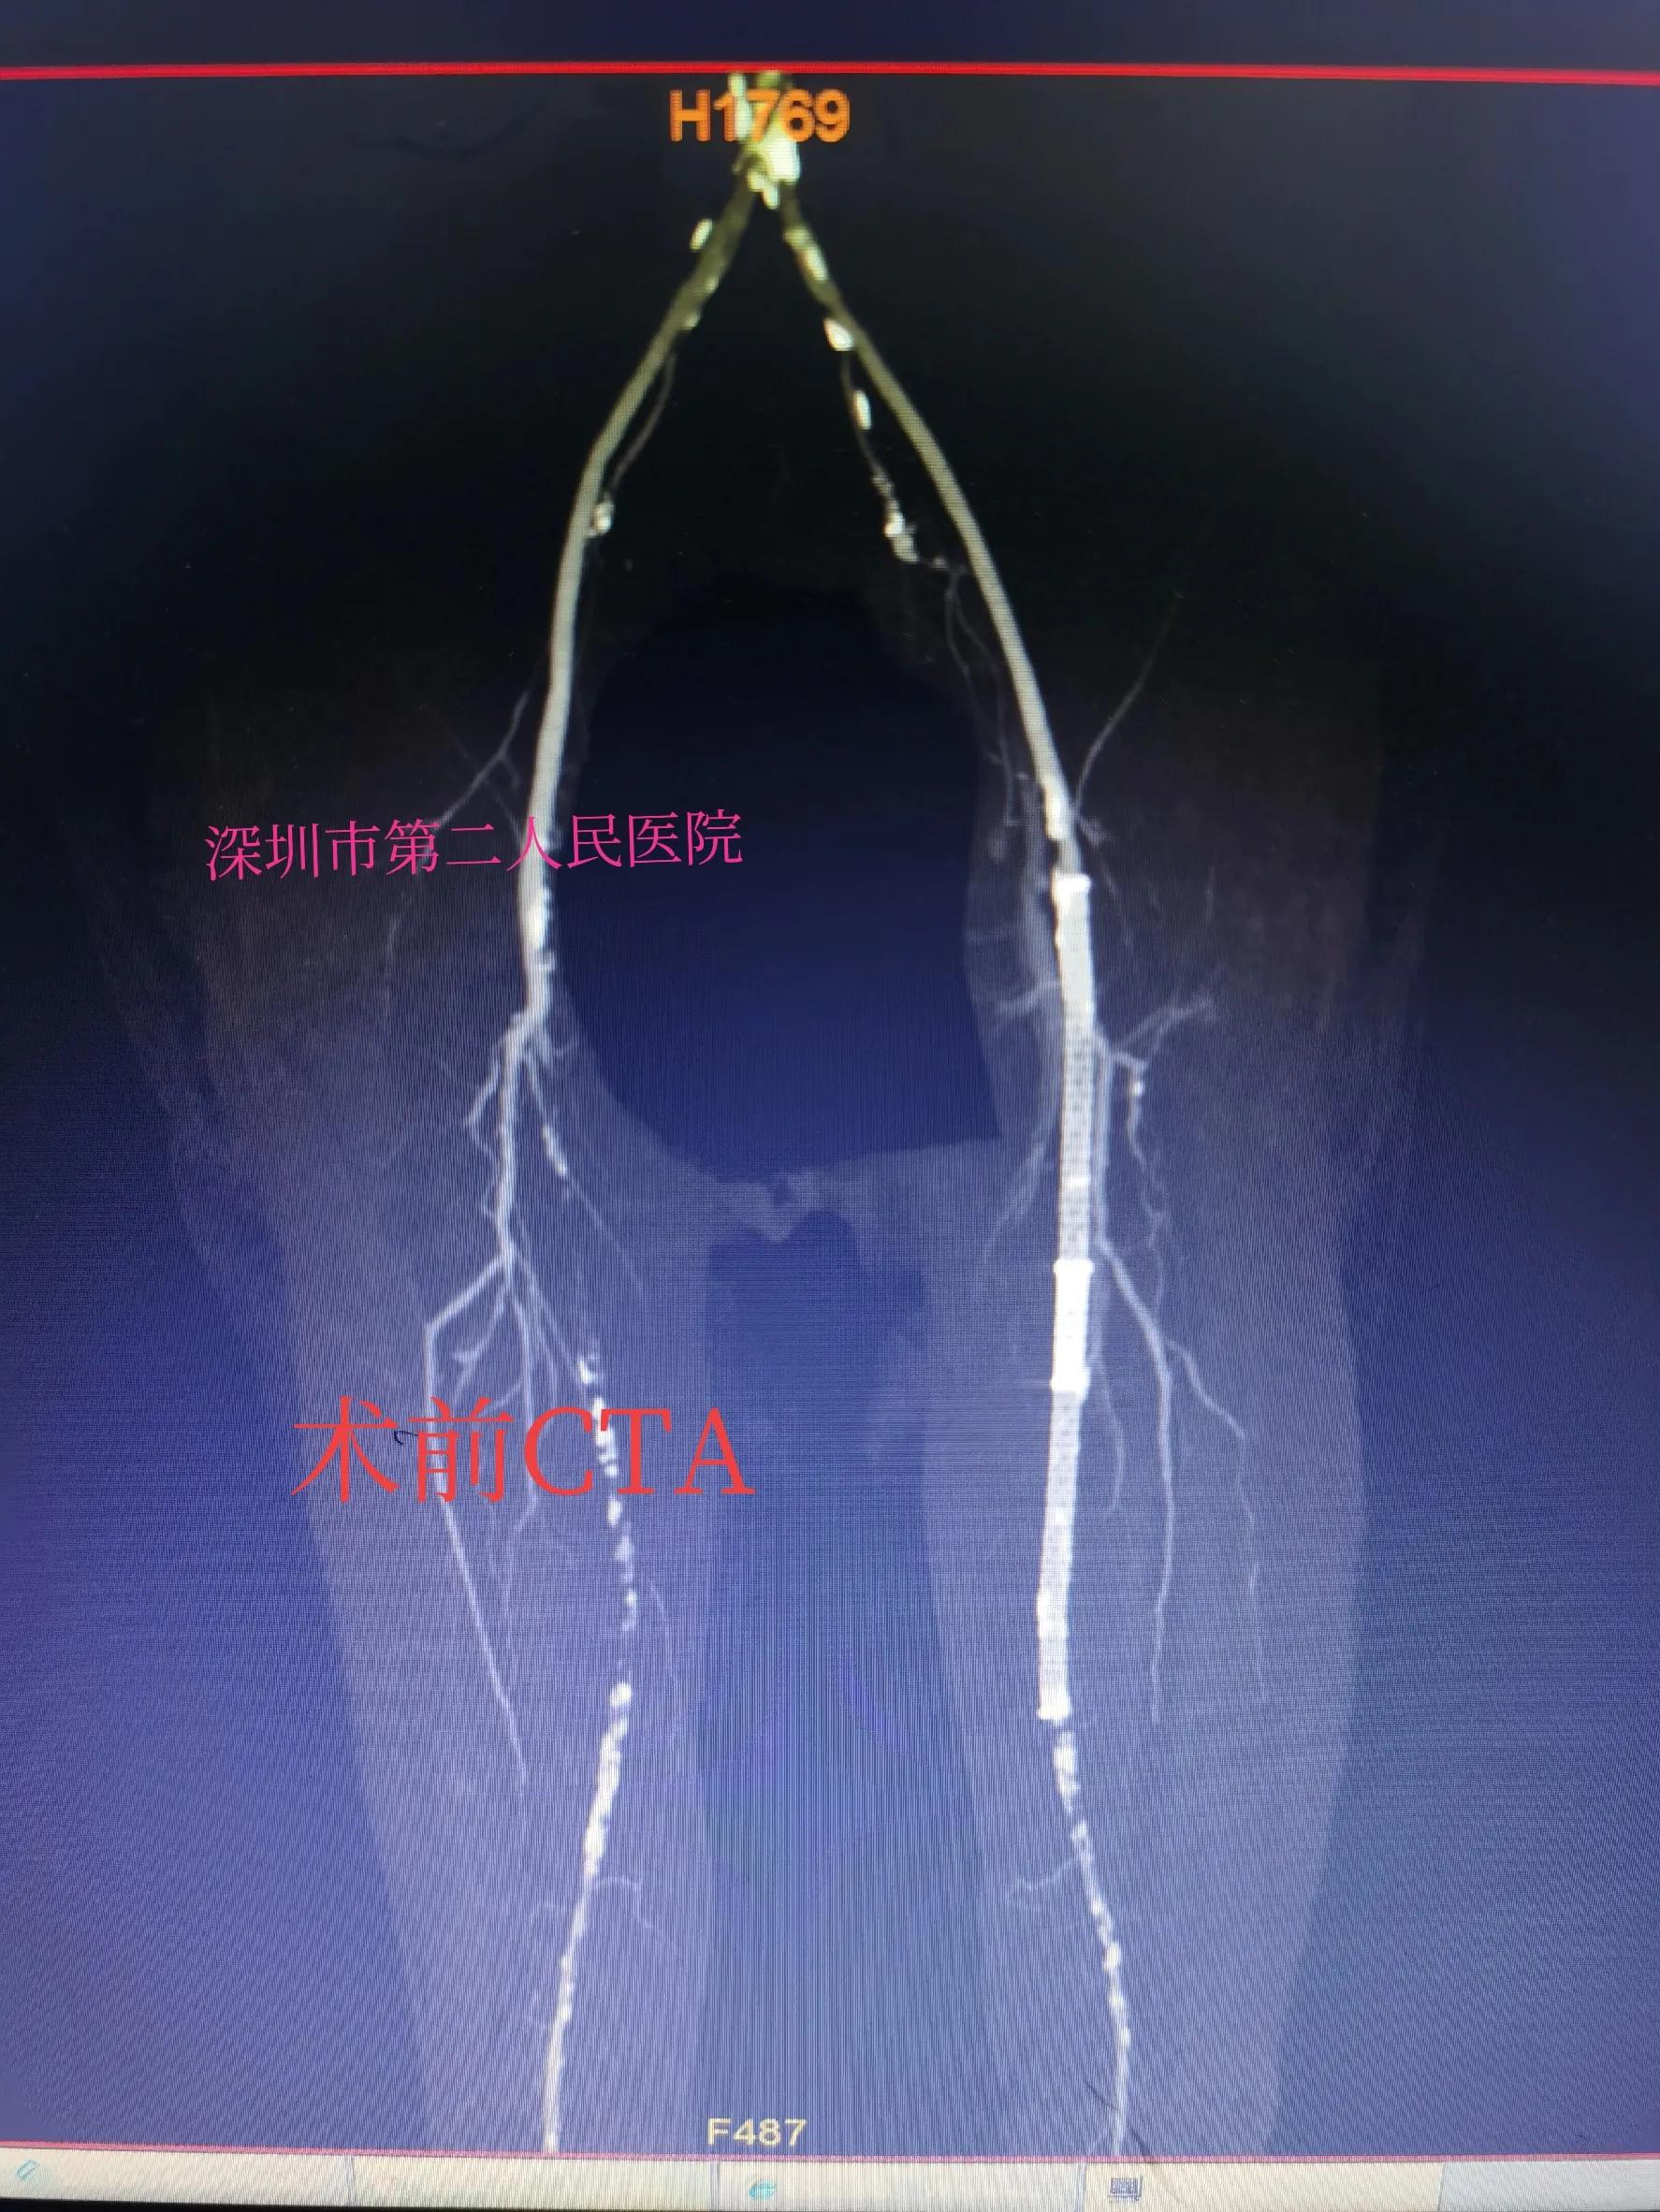

70的王奶奶有20多年糖尿病和5年高血压病史,去年在老家医院放过左腿的动脉支架,昨天晚上突然出现左小腿以下皮肤冰凉、发紫、疼痛难忍来急诊,做了彩超提示支架内血栓堵塞。紧急收住院做动脉CTA增强扫描,左小腿血管显影差,缺血严重,经过医生开会讨论后决定急诊手术开通堵塞的血管。

CTA提示左侧股浅动脉长段闭塞

支架堵塞